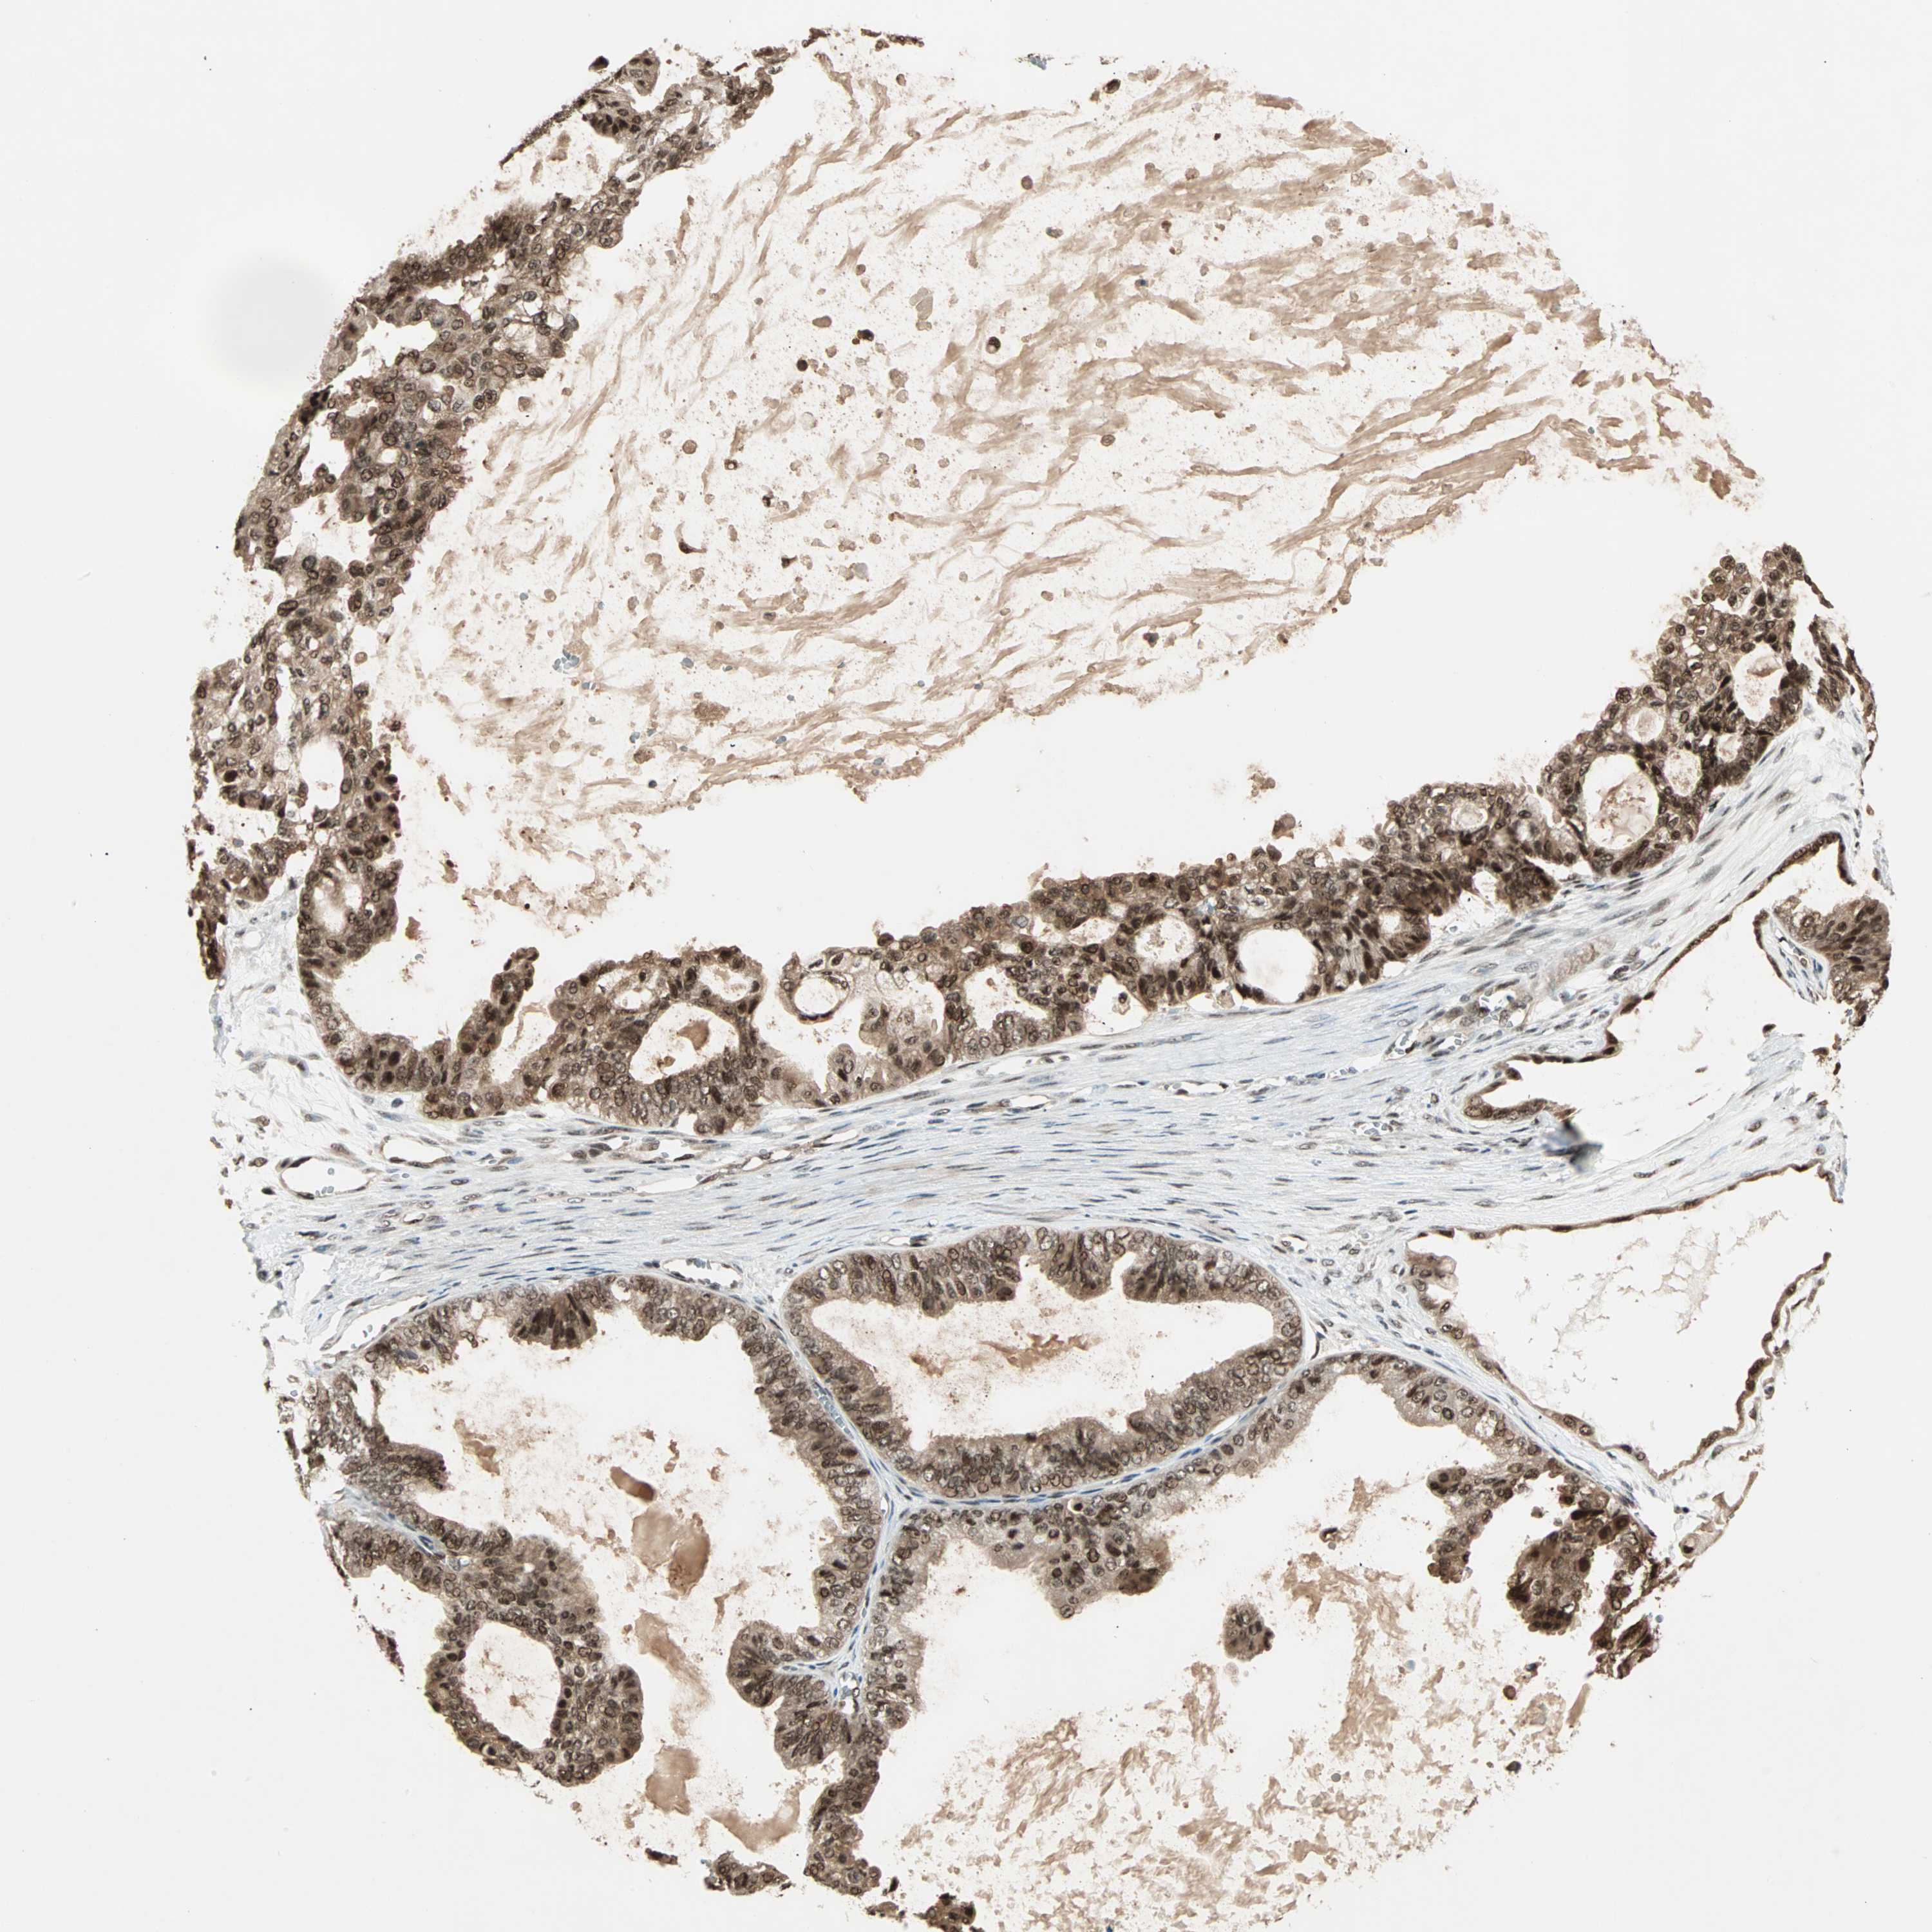

OVARIAN CANCER - Protein expressioni

A mouse-over function shows sample information and annotation data. Click on an image to view it in a full screen mode. Samples can be filtered based on level of antibody staining by selecting one or several of the following categories: high, medium, low and not detected. The assay and annotation is described here.

Note that samples used for immunohistochemistry by the Human Protein Atlas do not correspond to samples in the TCGA dataset.

Antibody stainingi

Antibody staining in the annotated cell types in the current human tissue is reported as not detected, low, medium, or high, based on conventional immunohistochemistry profiling in selected tissues. This score is based on the combination of the staining intensity and fraction of stained cells.

Each image is clickable and will lead to virtual microscopy that enables deeper exploration of all samples and also displays staining intensity scores, fraction scores and subcellular localization as well as patient and tissue information for each sample.

Antibody HPA003146

Staining

High

Medium

Low

Not detected

Intensity

Strong

Moderate

Weak

Negative

Quantity

>75%

75%-25%

<25%

None

Location

Nuclear

Cytoplasmic/membranous

Cytoplasmic/membranous,nuclear

Cystadenocarcinoma, serous, NOS

Carcinoma, endometroid

Carcinoma, NOS

Cystadenocarcinoma, mucinous, NOS